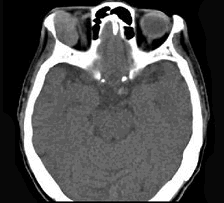

辅助检查中最有意义的发现是(如图)()

-